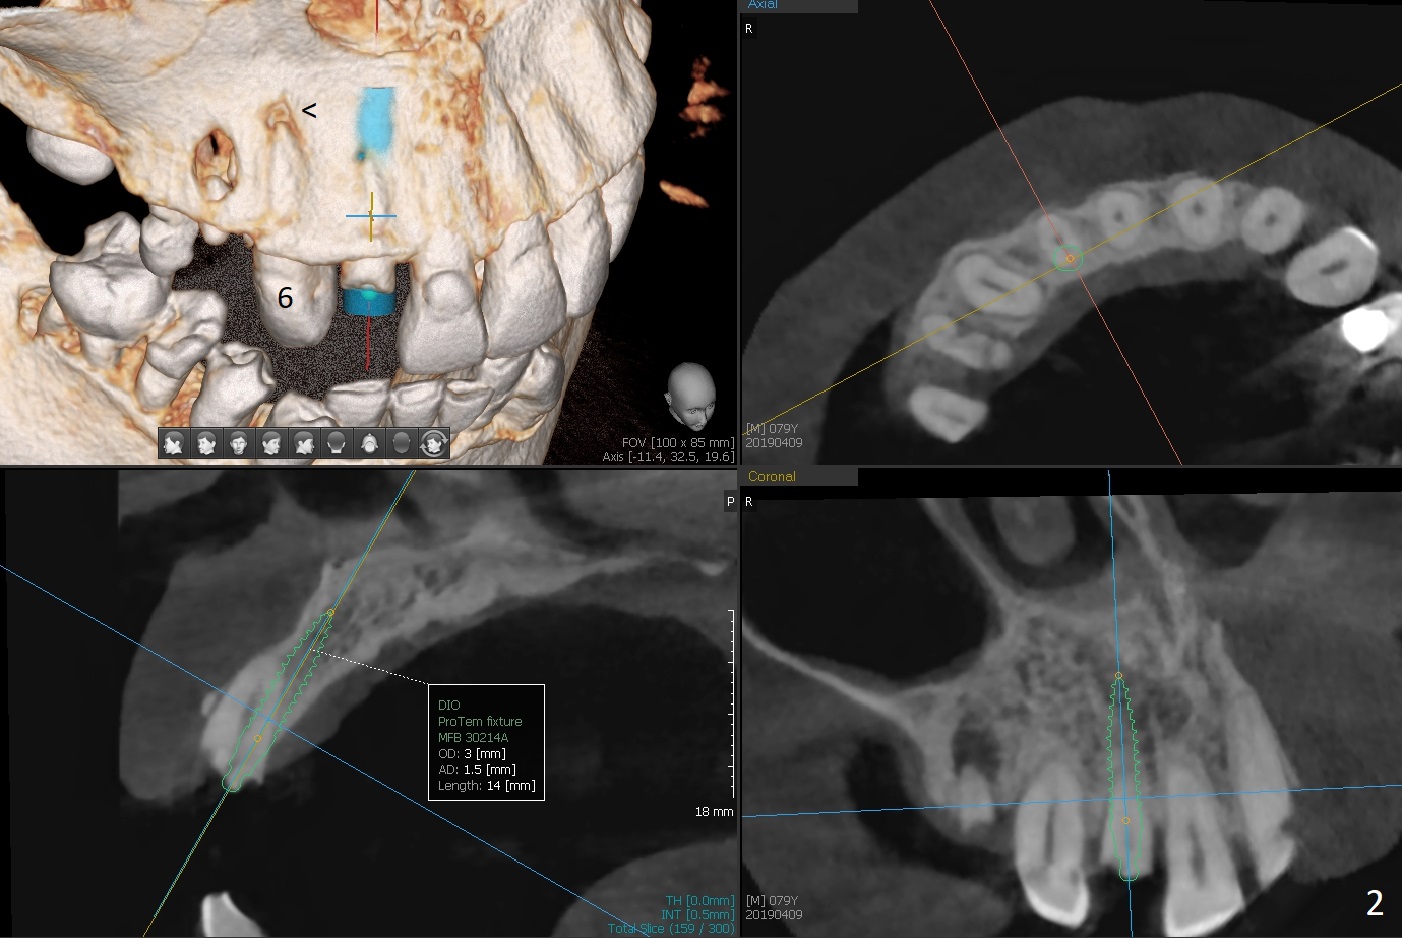

A 79-year-old man, who fractured the tooth #7, has several Class V defects (Fig.1). He seems to be a bruxer. Pay attention to occlusion and determine whether he has anterior deep bite. The neighboring tooth, #6, has apical lesion (Fig.2 <). Root canal therapy has been finished prior to implant placement (Fig.3). Prepare Tatum 1-piece implant in case the trajectory is off. If the crown height is more than 10 mm, prepare IS system. Otherwise use DIO one. If the root turns out to be difficult to extract, be ready for socket shield. Preop CT shows minimal apical perforation at #7 (Fig.4 (3-D image)). The buccal plate is thin (Fig.5 (coronal section) between arrowheads (acute infection may increase the perforation quickly)), while the crest is thick (*).